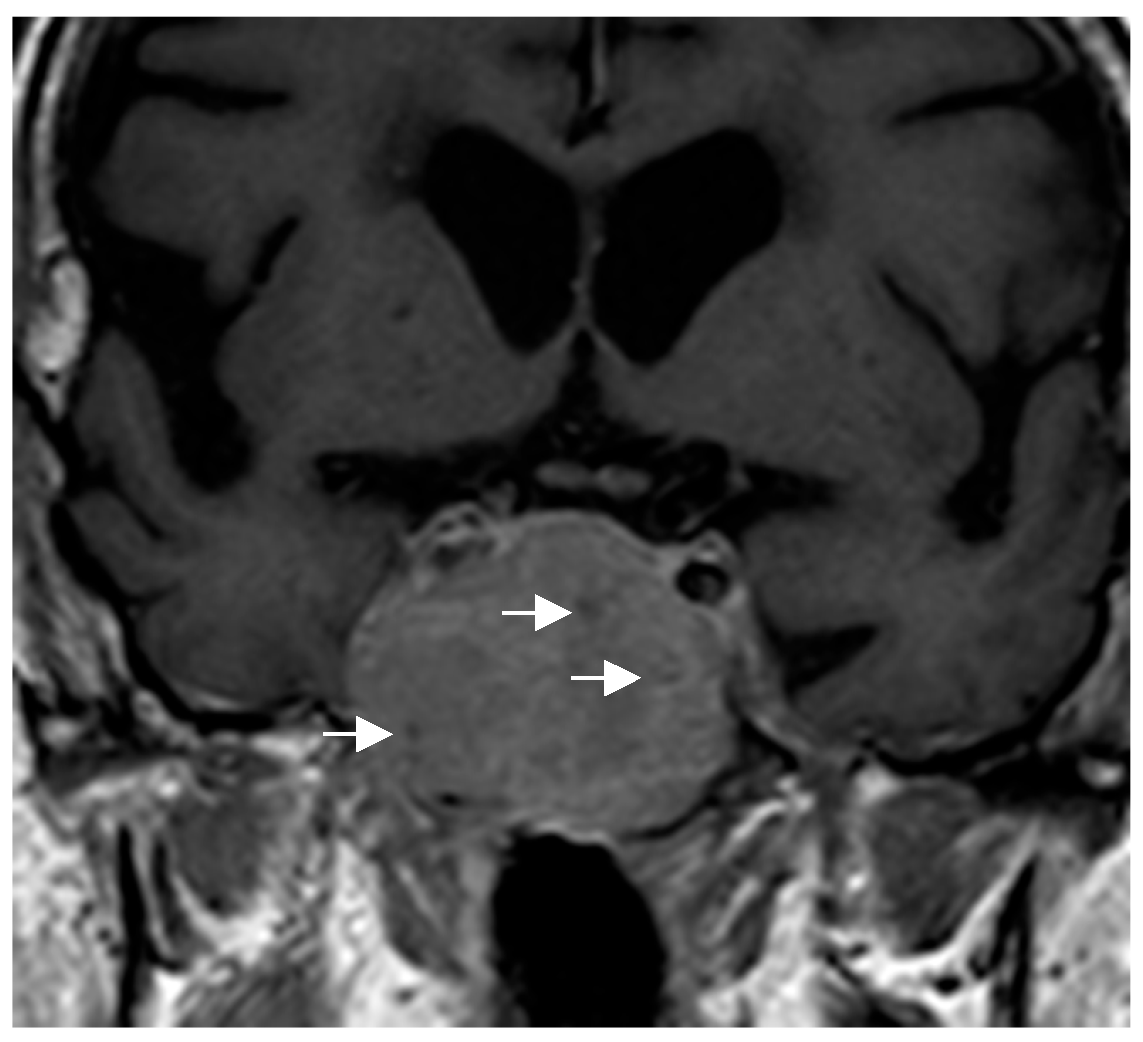

Because of their size and location, they can exert a mass effect on adjacent structures, including compression of the optic chiasm. Some authors have proposed specific radiological features that could guide the diagnosis: in PTC, this possibility should be considered in masses centered in the suprasellar region [50], while in GCTs, the diagnosis is suggested for very suprasellar or intra-suprasellar masses in which the posterior lobe of the pituitary is not identified on imaging [38,51]. In addition, GCTs may exhibit a characteristic pattern known as a “star-like crack”. This pattern is described as a series of linear structures that become convergent shapes, which appear as if they were cracks or lines radiating from a central point, giving the impression of a star [17]. With respect to SCO, the presence of multiple millimetric hypointense foci and linear T1 signal void areas (probably hemosiderin deposits and vascular structures, respectively) has been proposed as the most important distinctive radiological finding of SCO and may help to presuppose the diagnosis [52] (Figure 4). Given the small number of cases described, there is no information available to identify specific radiological characteristics of SE. In general, PPTs do not infiltrate the adjacent cavernous sinuses nor are they associated with significant cerebral edema, unlike other tumors in the region.

Figure 4. Coronal T1-weighted image showing an intra-suprasellar spindle cell oncocytoma (SCO). Multiple hypointense millimetric foci (white arrows) are seen in the lesion.